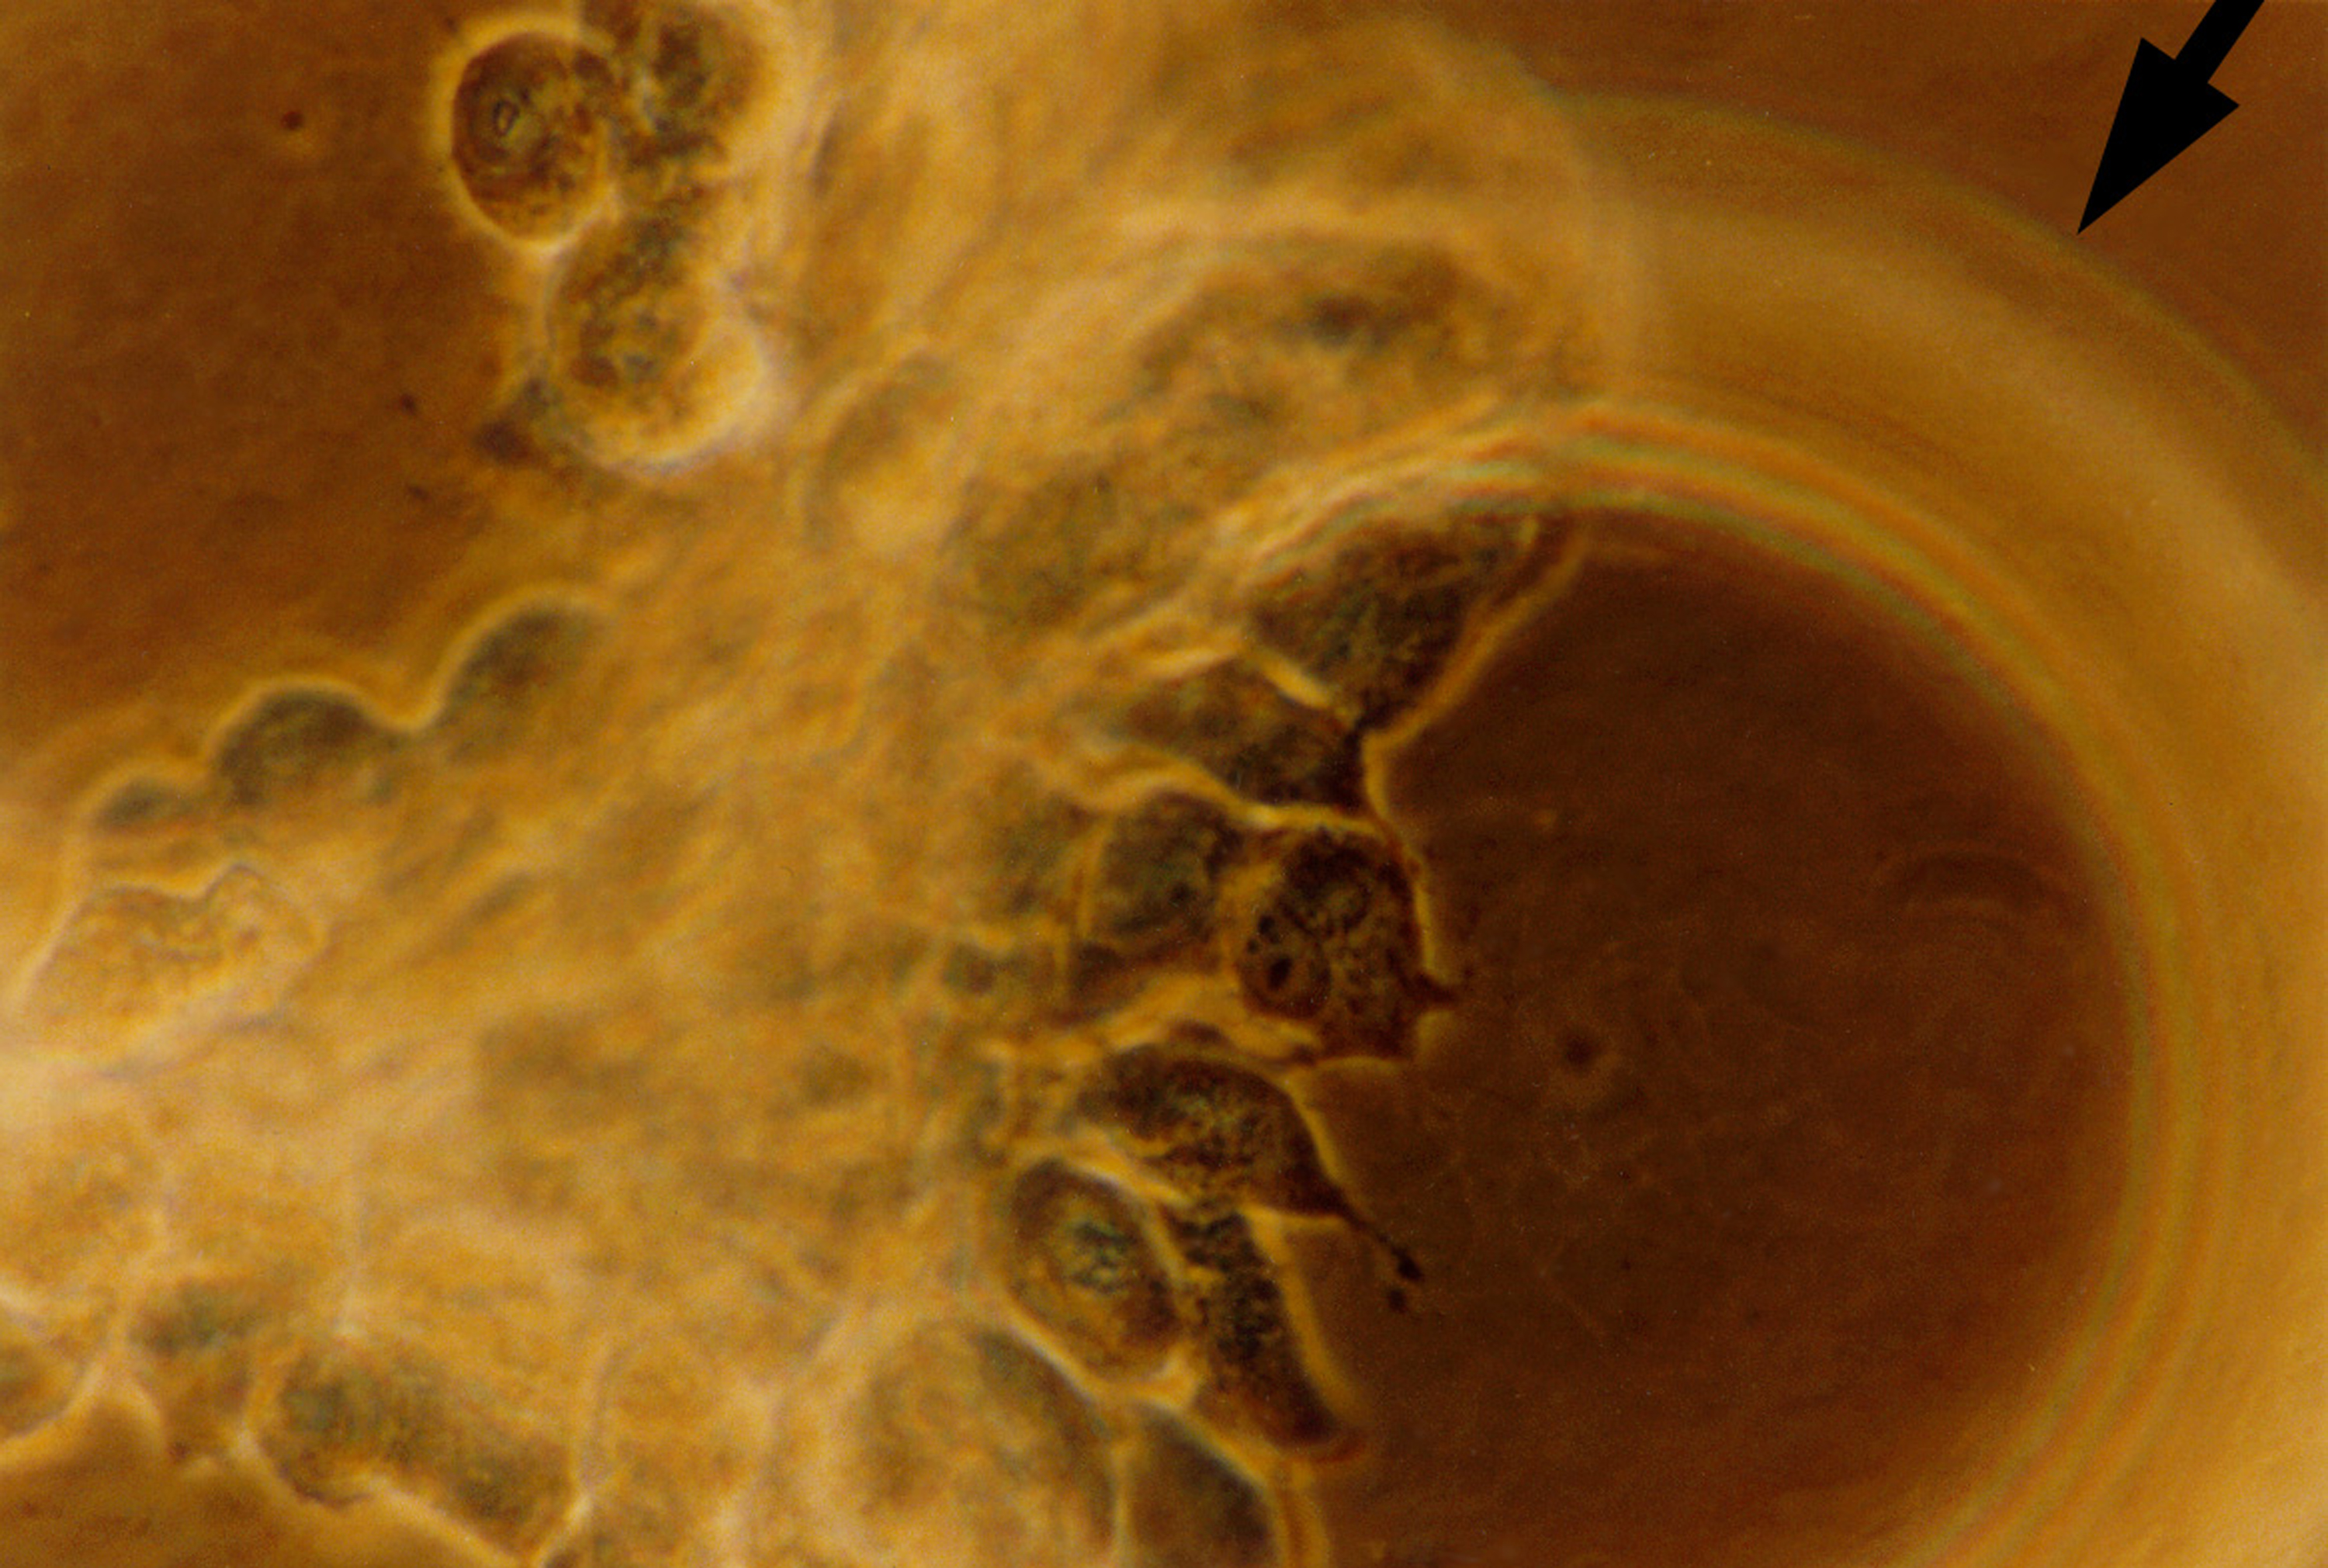

Human primary breast tumor cells after 49 days of growth in a NASA Bioreactor. Tumor cells aggregate on microcarrier beads (indicated by arrow). NASA's Marshall Space Flight Center (MSFC) is sponsoring research with Bioreactors, rotating wall vessels designed to grow tissue samples in space, to understand how breast cancer works. This ground-based work studies the growth and assembly of human mammary epithelial cell (HMEC) from breast cancer susceptible tissue. Radiation can make the cells cancerous, thus allowing better comparisons of healthy vs. tunorous tissue. Credit: Dr. Jearne Becker, University of South Florida